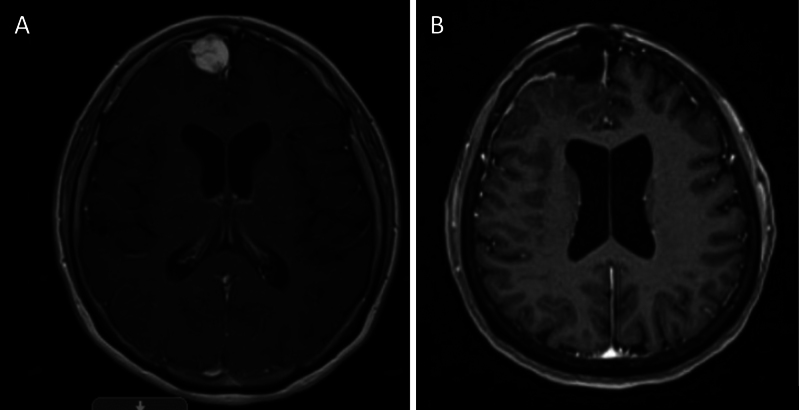

Background: Myxoid spindle cell neoplasm and meningioma are two different pathologies that can have similar radiographic findings. Despite their benign radiographic appearance, myxoid spindle cell neoplasms are heterogeneous, prone to recurrence, and associated with high mortality.

Observations: The authors present the case of a woman in her late 60s who experienced a witnessed seizure characterized by right arm tonic-clonic movements and subsequent left-sided manifestations. Initial radiographic findings were suggestive of a meningioma, but further investigation revealed a myxoid spindle cell neoplasm with a possible FET::CREB fusion. Pathologically, the tumor expressed desmin, EMA, and CD99, resembling meningiomas histologically.